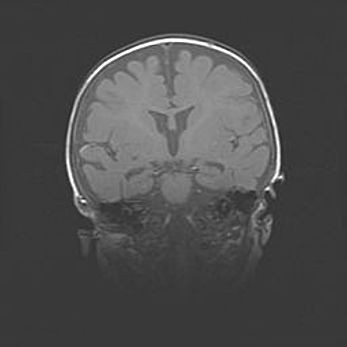

Наружная гидроцефалия с возможной атрофией височных областей.

Возраст: 28 дней

Вес: 3670 г

Пол: мужской

Окружность головы: 38 см

Срок гестации: 40 недель

Гидроцефалия головного мозга у новорожденных – это заболевание, которое характеризуется скоплением избыточного количества спинномозговой жидкости в желудочковой системе головного мозга в результате затруднения её перемещения от места выработки к месту поглощения в кровеносную систему или вследствие нарушения абсорбции. При открытой наружной форме гидроцефалии у новорожденных расширяются и переполняются субарахноидные пространства.

При нормотензивных  формах,  которые,  как  правило,  являются  следствием  перенесенных ишемических  повреждений  паренхимы  мозга,  возможно  сочетание микроцефалии  с нормотензивной гидроцефалией. В основе данных изменений лежит атрофия больших полушарий с преимущественной  локализацией  в  лобно-височных  областях.